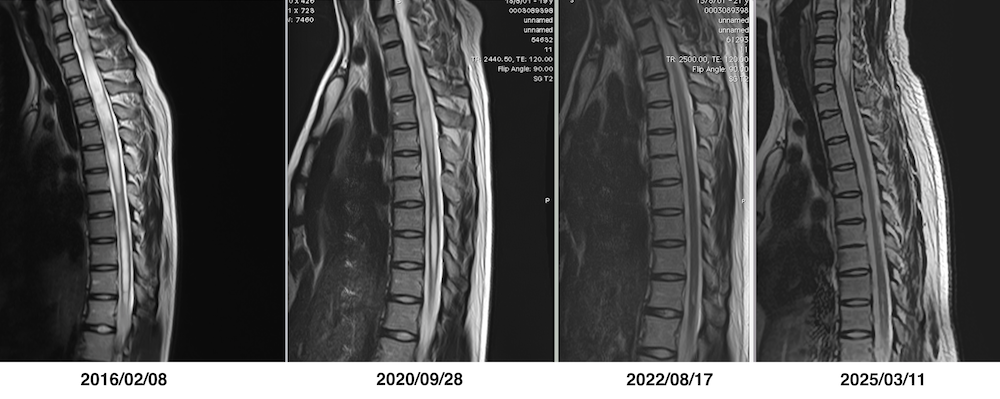

終糸切断手術後の頸髄および胸髄の脊髄空洞症の経過を示したMRI画像